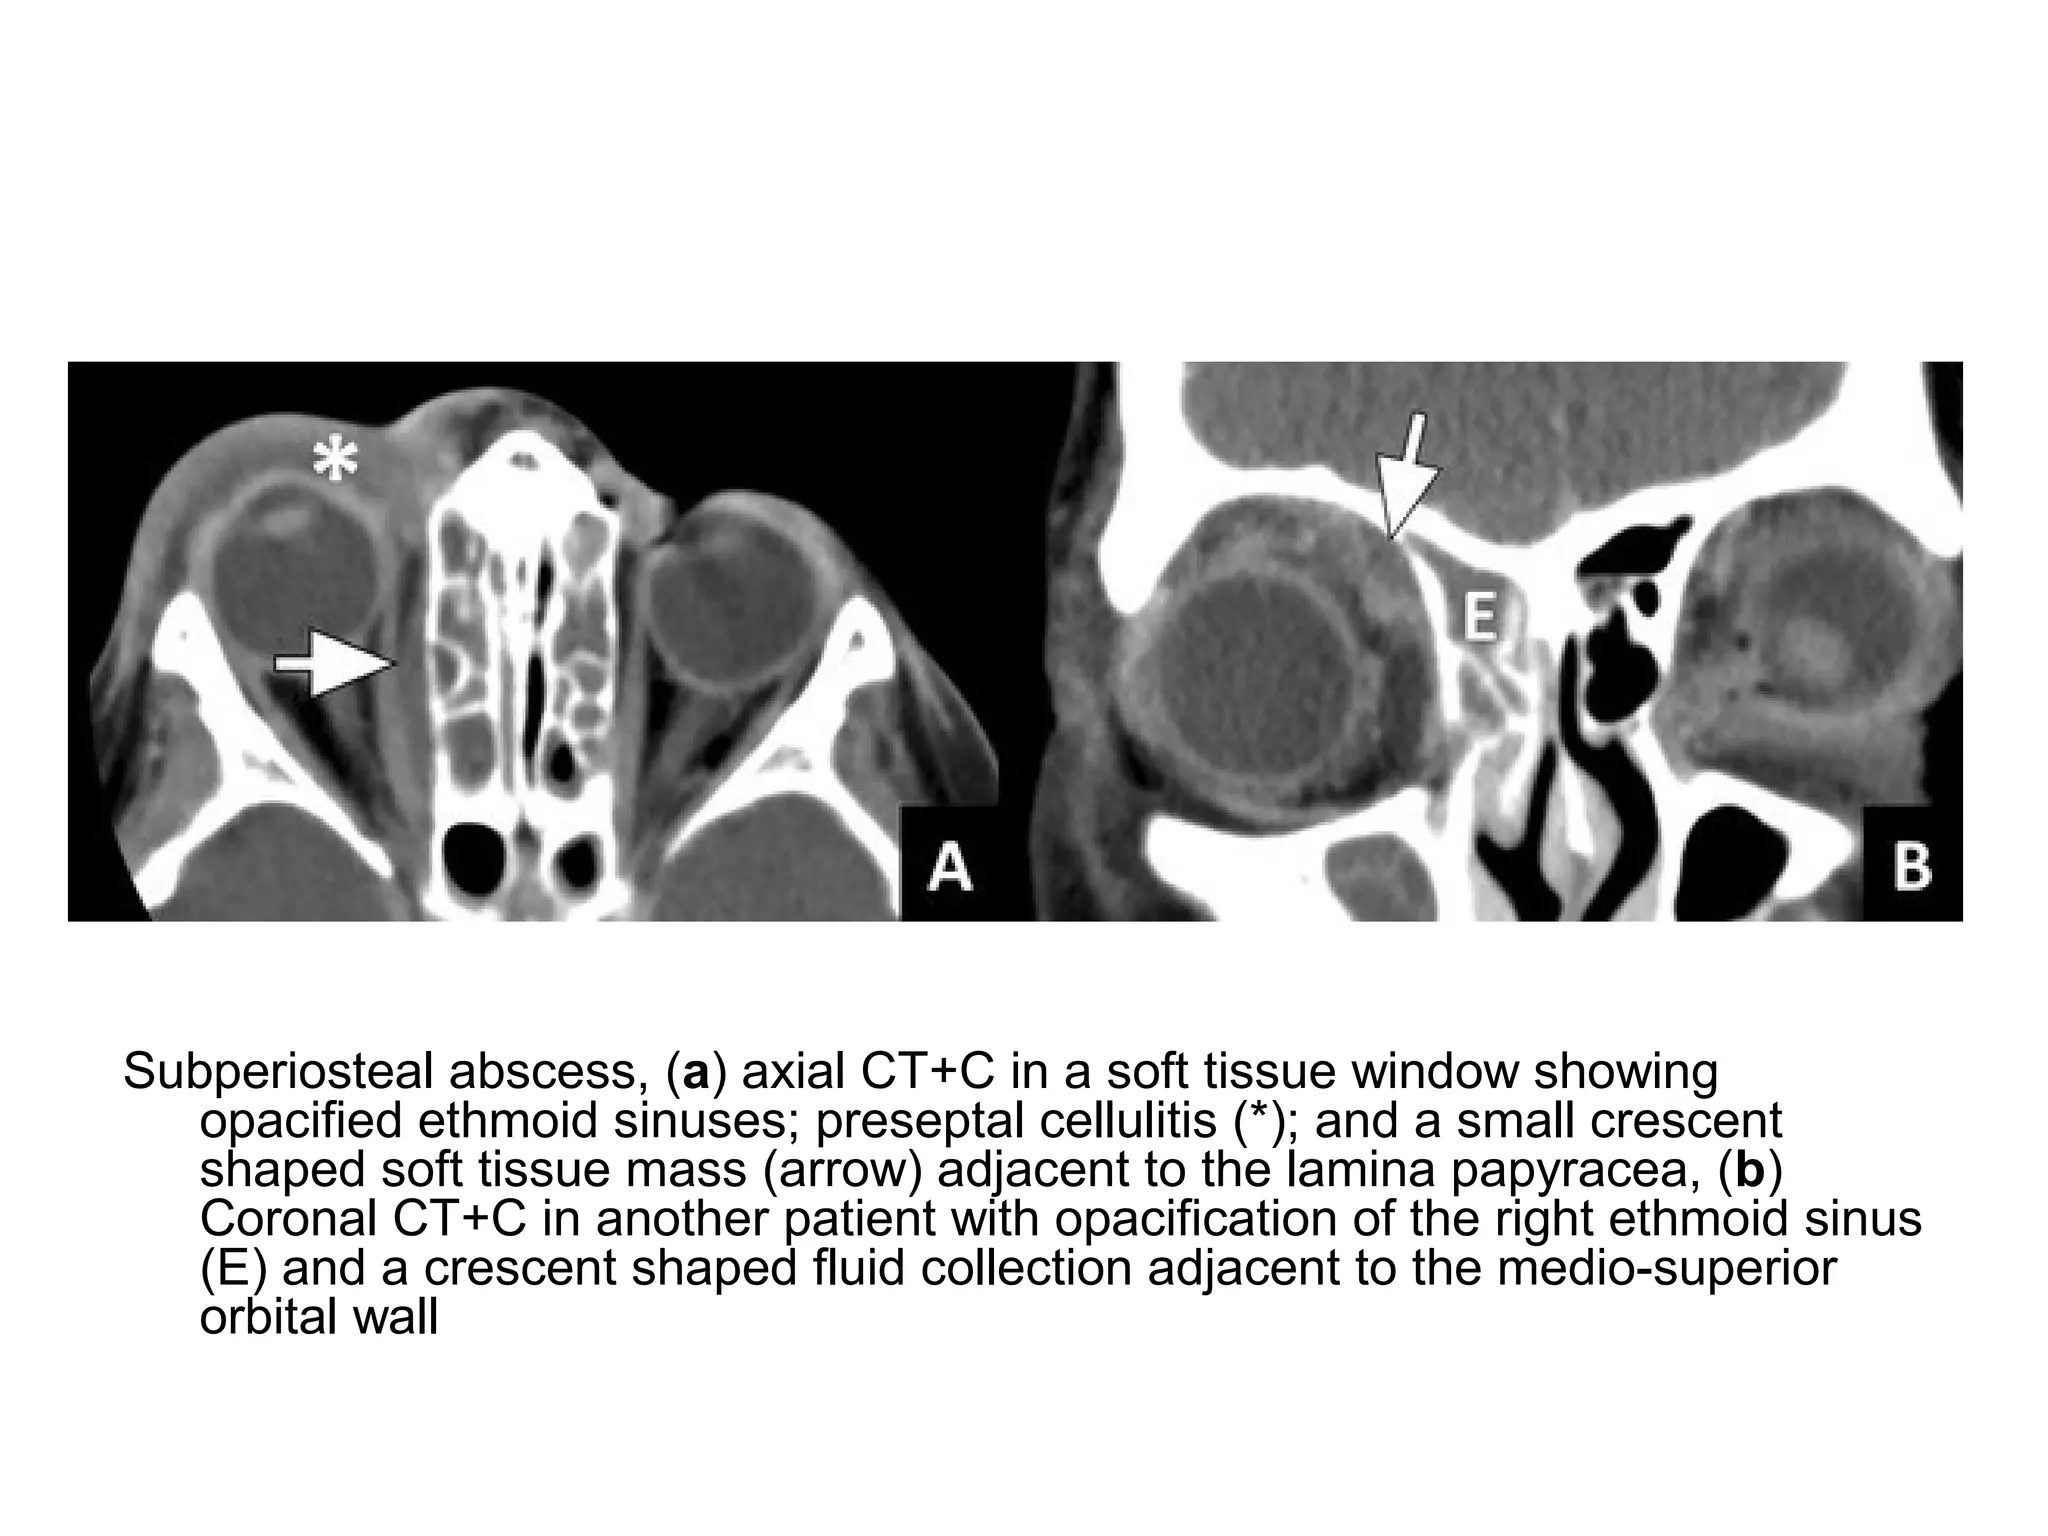

Subperiosteal abscess, (a) axial CT+C in a soft tissue window showing

opacified ethmoid sinuses; preseptal cellulitis (*); and a small crescent

shaped soft tissue mass (arrow) adjacent to the lamina papyracea, (b)

Coronal CT+C in another patient with opacification of the right ethmoid sinus

(E) and a crescent shaped fluid collection adjacent to the medio-superior

orbital wall